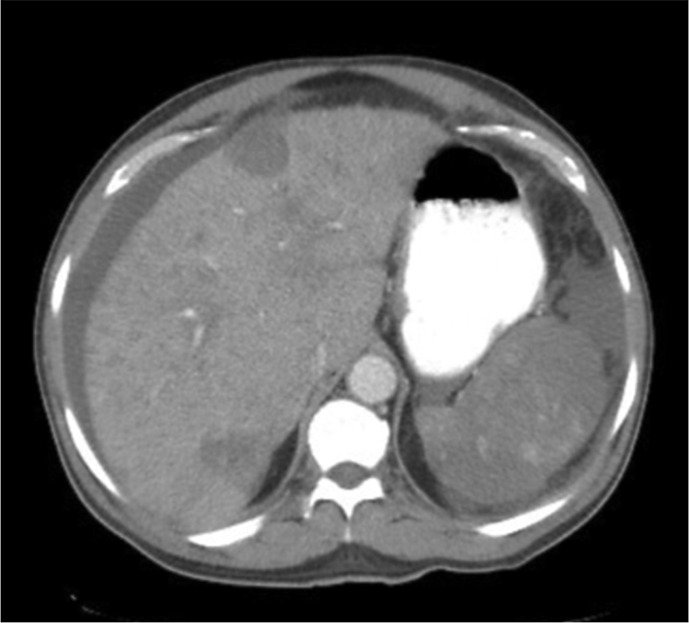

Case description: A 56-year-old male presented with 2 months of abdominal pain, distension, fatigue, and weight loss. Imaging revealed multifocal hypodense liver and splenic lesions. Laboratory findings included severe anemia (Hb 6.1 g/dL), thrombocytopenia (63 × 103/mm3), and elevated liver enzymes. Ascitic fluid analysis demonstrated exudative, bloody ascites (SAAG <1.1) without malignant cytology. Liver biopsy confirmed HAS, showing atypical spindle cells infiltrating vascular channels, positive for CD34 and factor VIII. Despite transfusions, paracentesis, and palliative care, the patient developed disseminated intravascular coagulation and died 2 weeks post-diagnosis.